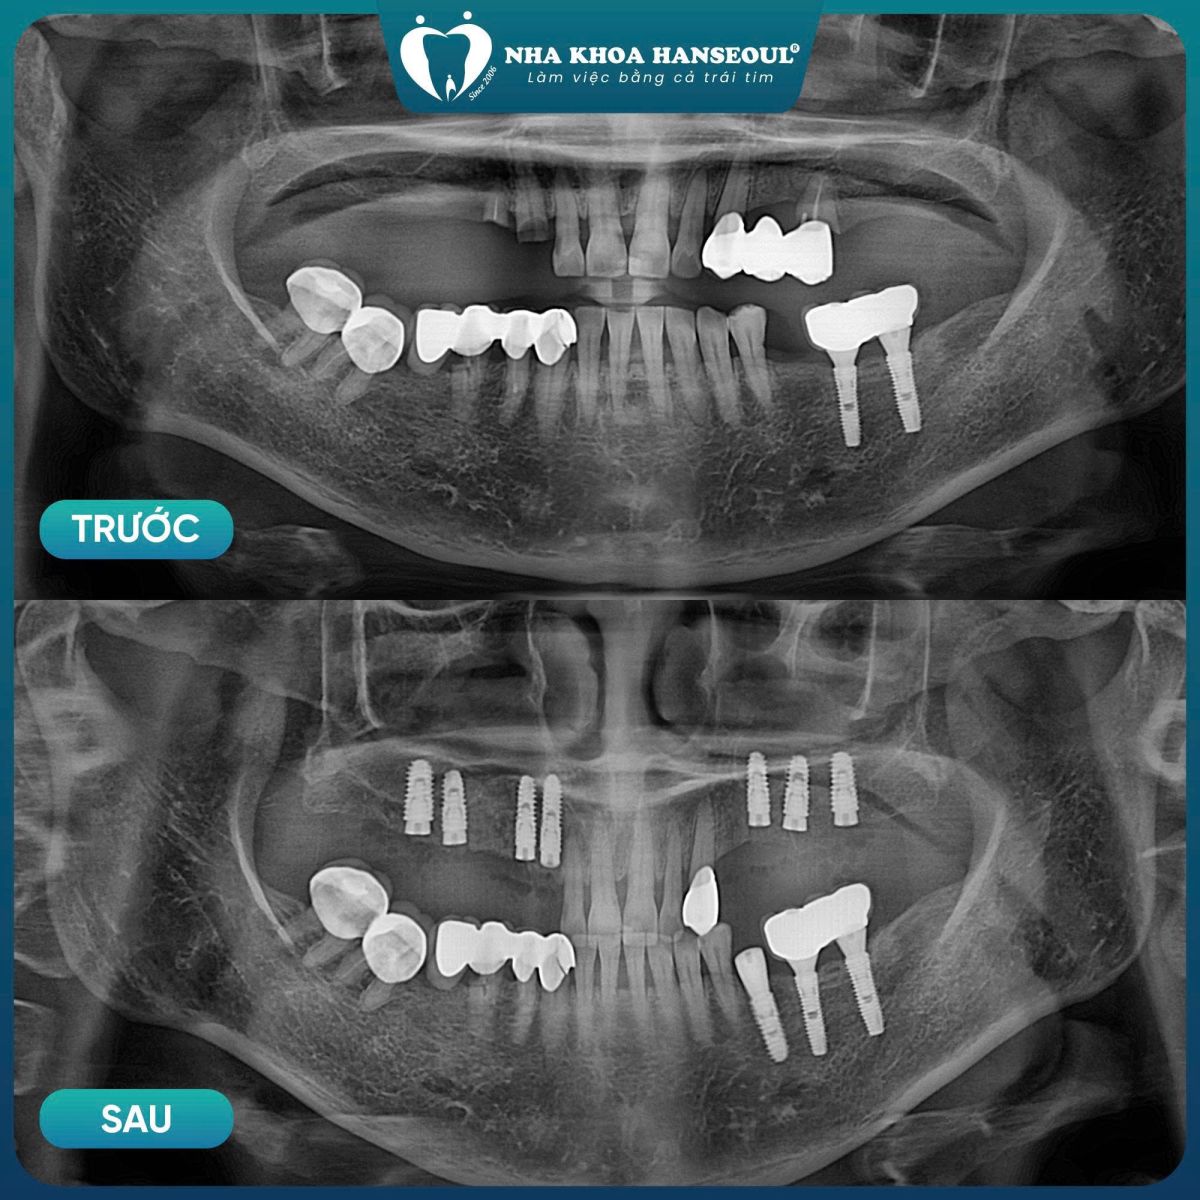

6 Kết quả sau điều trị – So sánh trước & sau

6.1 Trước điều trị

-

Ăn nhai hạn chế, phải tránh nhiều loại thực phẩm

Lực nhai yếu, phân bổ không đều

Nguy cơ tiêu xương tiếp diễn

Tâm lý dè chừng khi ăn uống

6.2 Sau cấy ghép Implant

Nền răng được phục hồi vững chắc

Lực nhai được tái lập, phân bổ cân bằng

Khả năng ăn nhai cải thiện rõ rệt

Khách hàng tự tin hơn trong sinh hoạt hằng ngày

Đối với cô Thái, sự thay đổi lớn nhất không chỉ nằm ở hàm răng, mà còn ở chất lượng cuộc sống: ăn uống thoải mái hơn, tinh thần nhẹ nhõm và an tâm về sức khỏe lâu dài.